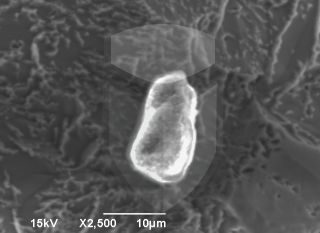

Lote de implante com muito ou coberto de alumínio na superfície.  Exclusivo para Pacote Premium

Jateado

Jateamento

Elemento(s)/Traço(s) na superfície:

Galeria de imagens